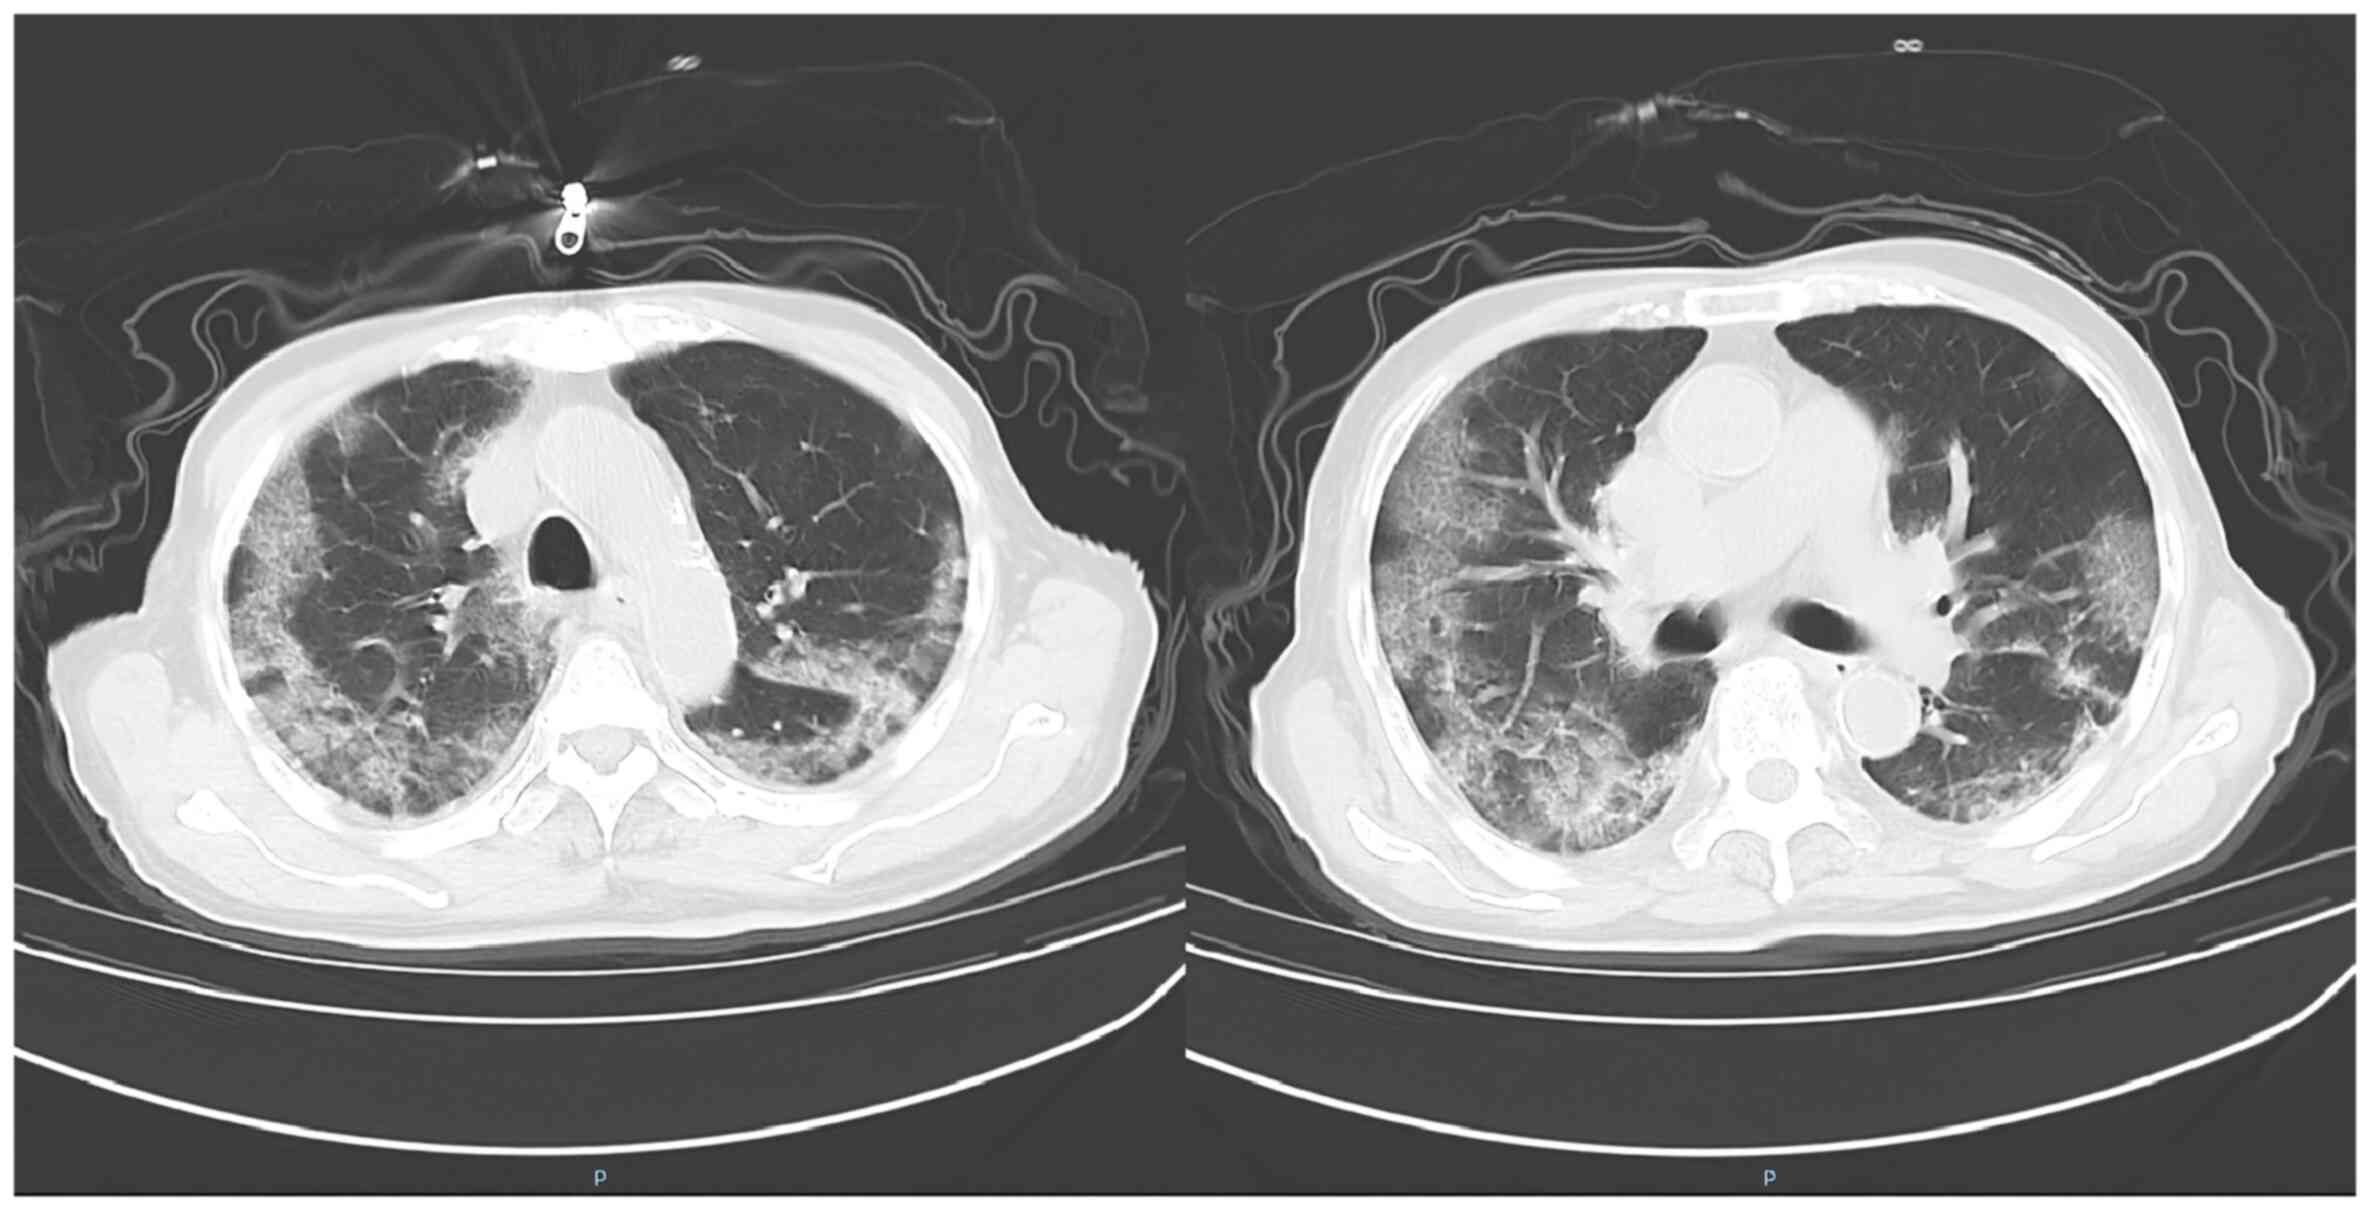

In January 2023, a 95-year-old man (weight, 54 kg) was admitted to the Department of Infectious Diseases (The First Affiliated Hospital of Anhui Medical University, Hefei, China) due to pneumonia. The results of a physical examination at admission included a temperature of 38.4˚C (normal range, 36-37˚C of axillary temperature), a pulse of 90 bpm (normal range, 60-100 bpm), a respiratory rate of 20 breaths/min (normal range, 12-20 breaths/min) and a blood pressure of 128/65 mmHg (normal range, 90-140/60-90 mmHg). The nucleic acid test for SARS-Cov-2 was positive after admission. The white blood cell count was 2.9x109/l, the percentage of neutrophils was 84.8%, the percentage of lymphocytes was 9.3%, the absolute value of lymphocytes was 0.27x109/l, the C-reactive protein level was 69.8 mg/l and the hemoglobin level was 119 g/l. The initial computed tomography scan (Fig. 1) showed bilateral pulmonary pneumonia. The diagnoses at admission were pneumonia and coronary atherosclerotic heart disease. The blood oxygen saturation was maintained at 86-92% with a 7 l/min high-flow mask providing centrally supplied oxygen. The partial pressures of carbon dioxide and oxygen were monitored using a transcutaneous partial pressure oxygen/carbon dioxide monitor (TCM CombiM; Radiometre Medical) on the left forearm (4,5). Patient transfer to the intensive care unit was not possible owing to the limited number of beds.

Figure 1

Computed tomography scans of the patient at different levels. Patchy fuzzy shadows with unclear boundaries and uneven internal density were observed in both lungs, especially in the lobus inferior pulmonis.